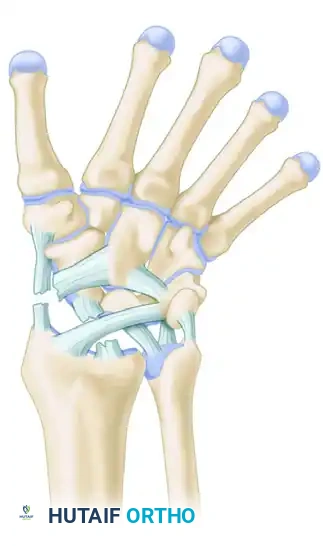

The human wrist is an intricate biomechanical marvel, comprising eight carpal bones, multiple articulating surfaces, and a complex network of intrinsic and extrinsic ligaments. The diagnosis of wrist conditions—whether acute traumatic injuries or chronic degenerative pathologies—demands a meticulous, systematic approach. For the orthopaedic surgeon, mastering the diagnostic algorithm is paramount to preventing long-term sequelae such as carpal collapse, chronic instability, and post-traumatic osteoarthritis (e.g., Scapholunate Advanced Collapse [SLAC] or Scaphoid Nonunion Advanced Collapse [SNAC]).

To accurately diagnose wrist instability, the surgeon must possess a profound understanding of carpal kinematics. Two primary biomechanical models dominate contemporary orthopaedic thought: Taleisnik’s Columnar Concept and Lichtman’s Ring Concept.

Taleisnik proposed that the wrist functions via three distinct longitudinal columns:

* The Central (Flexion-Extension) Column: Comprises the entire distal carpal row (trapezium, trapezoid, capitate, hamate) and the lunate. This column is primarily responsible for the transmission of flexion and extension forces.

* The Lateral (Mobile) Column: Consists solely of the scaphoid, which bridges the proximal and distal rows, providing critical stability and mobility.

* The Medial (Rotary) Column: Comprises the triquetrum, functioning as a pivot point for carpal rotation.

Lichtman’s Ring Concept

Lichtman expanded upon carpal kinematics by describing the carpus as an oval ring. In this model, the proximal and distal carpal rows act as semirigid posts stabilized by robust interosseous ligaments.

* Normal, controlled mobility occurs primarily at the scaphotrapezial and triquetrohamate joints.

* Pathomechanics: Any break in this ring—whether osseous (e.g., scaphoid fracture) or ligamentous (e.g., scapholunate dissociation)—destabilizes the kinematic chain.

The Dorsal Approach to the Wrist

The dorsal approach provides excellent exposure to the proximal carpal row, midcarpal joint, and distal radius.

1. Incision: A longitudinal incision is made centered over Lister’s tubercle, extending from the distal radius to the base of the third metacarpal.

2. Dissection: The extensor retinaculum is exposed. The third extensor compartment is opened, and the EPL tendon is transposed radially.

3. Retinacular Flaps: The second and fourth compartments are elevated subperiosteally to preserve their gliding layers.

4. Capsulotomy: A ligament-sparing capsulotomy (e.g., Berger’s dorsal intercarpal ligament-splitting approach or a tissue-preserving flap) is performed to expose the radiocarpal and midcarpal joints.

5. Intervention: Direct repair of the SL ligament using suture anchors, combined with dorsal capsulodesis if necessary. The carpus is anatomically reduced and stabilized with multiple 0.045-inch or 0.062-inch Kirschner wires (K-wires).

6. Closure: The capsule is meticulously repaired to prevent dorsal intercalated instability. The EPL is left transposed in the subcutaneous tissue to prevent attrition rupture.